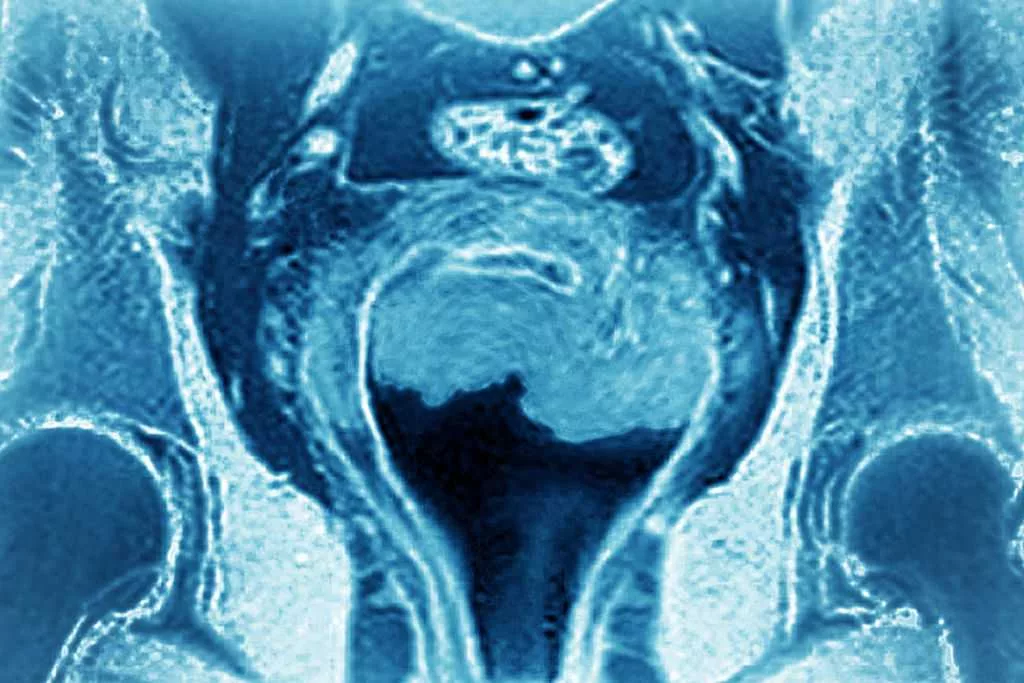

Uterine cancer among most common forms of cancer. A doctor explains what to know about it

Uterine cancer is one of the most common forms of cancer, and there are two distinct types.